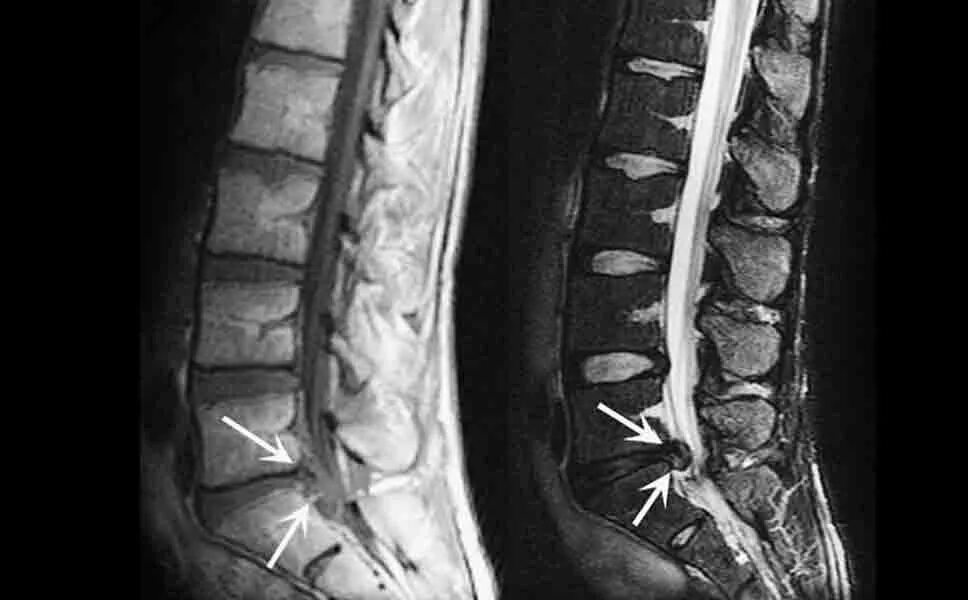

Грыжа 4 5